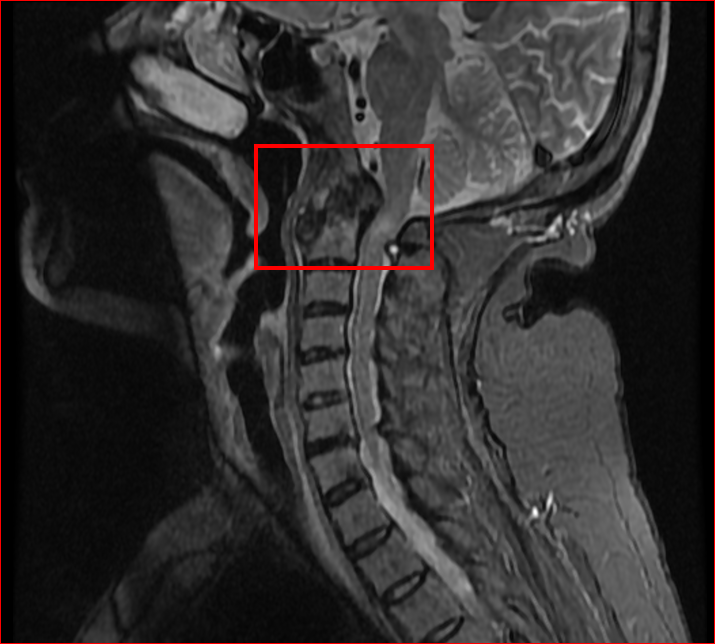

术前颈椎核磁:寰枢椎脱位,颈髓变性,颅底凹陷

患者刘阿姨患类风湿性关节炎30余年,同时患有继发寰枢椎脱位、类风湿性寰枢关节炎、颅底凹陷、颈髓变性,长期受头痛头晕、双手麻木、行走不稳等症状困扰,严重影响生活质量。曾四处求医,但因病情复杂,很多医院束手无策,症状逐渐加重。后来,经人推荐来到通州区中西医结合医院脊柱创伤科王德成主任专家门诊就诊。王主任带领科室团队对患者进行了详细的术前检查和查体,邀请医务科、内科、麻醉科、眼科等多科室进行缜密的术前多学科会诊和风险评估,经过反复讨论最终制定了精密的颈枕融合内固定手术治疗方案,完善术前准备。在外请专家指导下,王德成主任和贺志亮主治医师及麻醉科、检验科、手术室的密切配合和全力护航下,成功为患者实施手术。